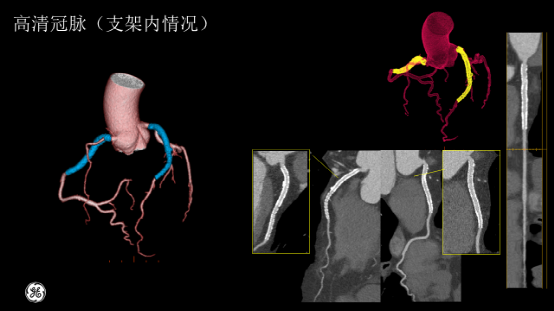

患者图像质量显示完美,

没有任何搏动伪影,血管显示清晰,

来吧,一起看图~

血管显示清晰,没有搏动伪影

回旋支近端软斑块并管腔轻度狭窄

RCA右冠状动脉多发软斑块并管腔轻度狭窄